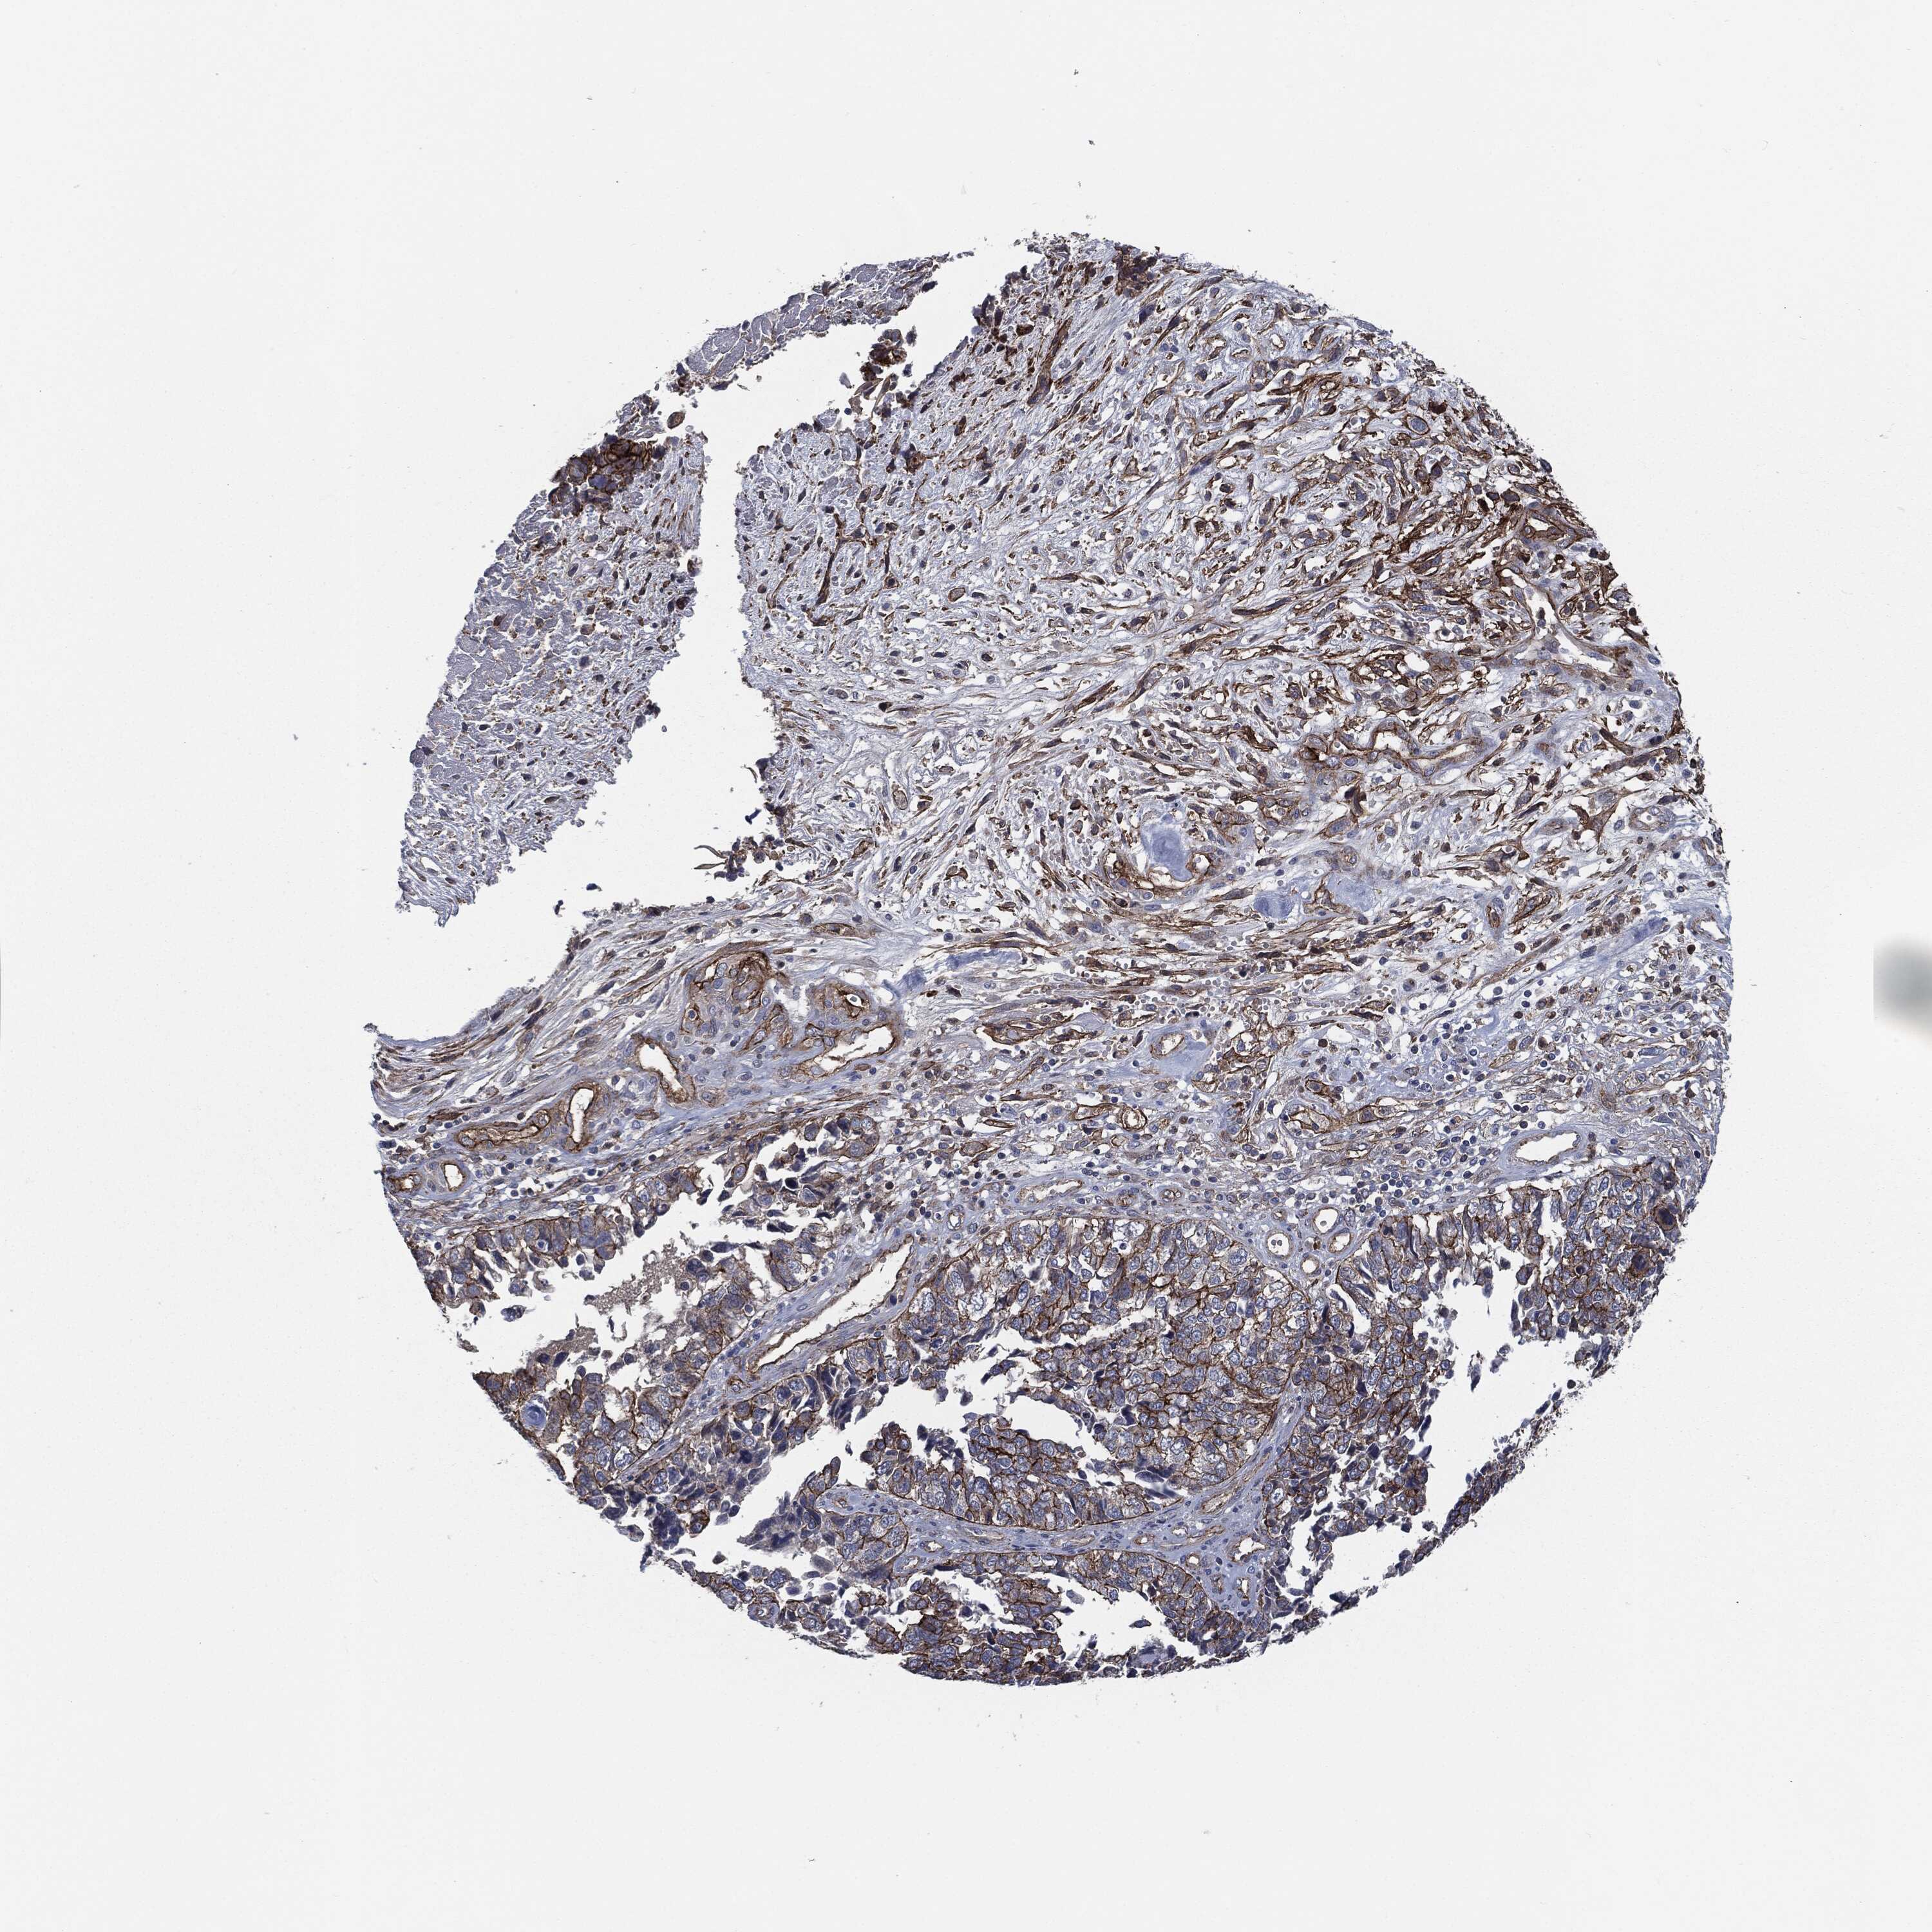

CERVICAL CANCER - Protein expressioni

A mouse-over function shows sample information and annotation data. Click on an image to view it in a full screen mode. Samples can be filtered based on level of antibody staining by selecting one or several of the following categories: high, medium, low and not detected. The assay and annotation is described here.

Note that samples used for immunohistochemistry by the Human Protein Atlas do not correspond to samples in the TCGA dataset.

Antibody stainingi

Antibody staining in the annotated cell types in the current human tissue is reported as not detected, low, medium, or high, based on conventional immunohistochemistry profiling in selected tissues. This score is based on the combination of the staining intensity and fraction of stained cells.

Each image is clickable and will lead to virtual microscopy that enables deeper exploration of all samples and also displays staining intensity scores, fraction scores and subcellular localization as well as patient and tissue information for each sample.

Antibody HPA020095

Antibody HPA020138

Antibody CAB010878

Antibody CAB080402

Staining

High

Medium

Low

Not detected

Intensity

Strong

Moderate

Weak

Negative

Quantity

>75%

75%-25%

<25%

None

Location

Nuclear

Cytoplasmic/membranous

Cytoplasmic/membranous,nuclear

Squamous cell carcinoma, NOS

Adenocarcinoma, NOS